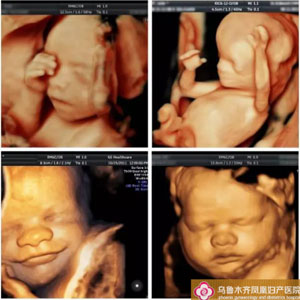

凤凰妇产医院:四维彩超是超声检查的一种,除了一般彩超的功能外,还可以进行胎儿头面部立体成像,可清晰地显示眼、鼻、口、下颔等状态,可协助医生直接对胎儿先天畸形进行诊断,包括表面畸形、内脏畸形和头面部畸形,能确定胎儿在子宫中的精确位置。

凤凰妇产医院:四维彩超与一般超声检查相比,四维彩超在超声诊断方面具有四维图像成像速度快、图像清晰、分辨率高等优势,能够多方位、多角度地观察宫内胎儿的生长发育情况,为早期诊断胎儿先天性体表畸形和先天性心脏疾病提供更为准确的依据。

普通B超只能检查出胎儿的部分生理指标,四维彩超能够对胎儿进行较系统的全面的检查。四维彩超超声系统代表着当今世界超声医疗领域的最前沿,已经过反复研究、测试,实践证明它是安全的。通过胎儿的动态图像显示增进母子之前的感情。

凤凰妇产医院:四维彩超还能让准爸妈提前跟胎宝宝“见面”,看到胎儿在母体内的实时动态,如微笑、打呵欠、皱眉头、做鬼脸、吸手指、伸懒腰、吐舌头等,这些都是一般的B超无法做到的。四维彩超能动态的记录胎宝宝在母体里成长的珍贵时刻,还能制作成光盘,让宝宝拥有今生只有一次的0岁相册,留下永久的记忆。